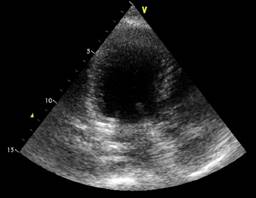

The initial LVEF was 36%, and 48 hours later, it was 47% (Figure 1). The echocardiogram showed important dilation of the left ventricle (Figure 2). The echocardiographic controls performed on the tenth day, at seven and 12 months, showed recovery and normal LVEF, demonstrating complete reversibility at 10 days that continues up to one year (Figure 3). There was no compromise in cardiac output according to measurements in the five echocardiograms performed. The cardiac index was calculated using the Dubois cardiac index estimation formula; the cardiac index was not altered during the development of the pathology.22 GLS is also used to assess left ventricular systolic function in patients with septic shock. It detects subtle changes in myocardial contractility and is more sensitive and accurate in evaluating systolic ventricular function compared to LVEF. We obtained a GLS of -14% initially (Figure 4); in the 12th month of echocardiographic control, normalization of the values was found with a GLS of -20.6% (Figure 5), therefore recovery of systolic function, which is considered normal at values of -18% to -20%. Measurement of variables through direct methods was not possible.

Figure 2: An apical 3-chamber view of the echocardiogram was performed after 48 hours, where spherical dilation of the left ventricle was observed.